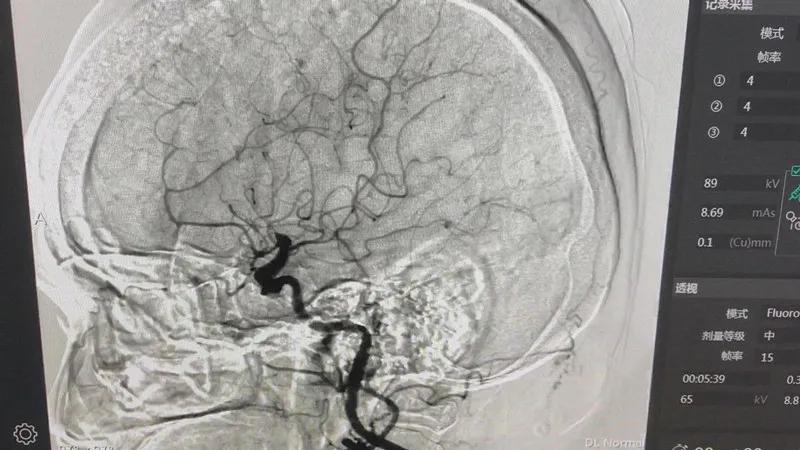

“DSA可以说是一台救命的机器。它通过X光机可以清楚地看到心脏的血管和脑血管及其他脏器的血管分布走形有没有发生病灶,可以用于冠心病的诊断治疗,特别是急性心肌梗塞、脑梗塞的黄金时间救治。”新津区人民医院副主任医师、急诊科主任杨卓介绍说。

脑血管造影术(DSA)

数字减影血管造影简称DSA,即血管造影。DSA是近年来广泛应用于临床的一种崭新的X线检查新技术,它通过动脉注入含碘造影剂,造影剂所经过的血管轨迹连续摄片,通过电子计算机辅助成像为脑血管数字减影造影(DSA)。DSA引导下的介入治疗目前已经成为治疗血管瘤、脉管畸形等疾病的主流方法之一,甚至被认为是治疗血管瘤的王牌利器。